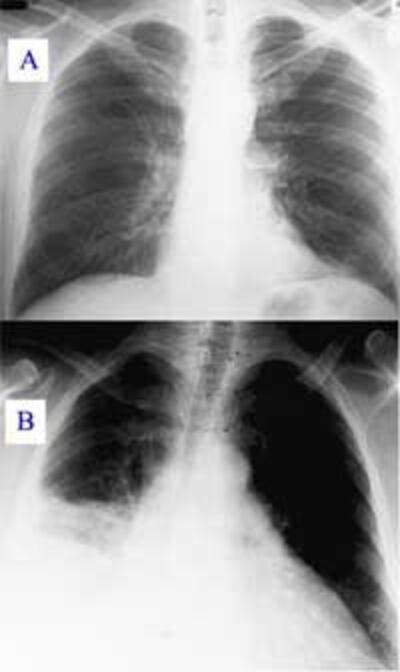

“Viêm phế quản mạn được định nghĩa là tình trạng ho có đàm ít nhất ba tháng liên tiếp trong vòng ít nhất hai năm liên tiếp. Đặc điểm của bệnh này là sự gia tăng bài tiết các chất nhầy trong cuống phổi. Đây là một trong những yếu tố nguy cơ dẫn đến viêm phổi, đặc biệt là với loại vi trùng có tên là Haemophilus influenzae.

Viêm phổi là bệnh thường gặp và thường gây tử vong nhất ở Việt Nam. Điều quan trọng nhất để tránh biến chứng và giảm tỉ lệ tử vong là phát hiện sớm và chữa bệnh sớm. Điều quan trọng cần chú ý khi chữa bệnh là dùng đúng loại và đủ liều kháng sinh, nâng đỡ cơ thể bằng cách giữ vệ sinh, ăn uống đủ dinh dưỡng, và chữa các triệu chứng. Cần đến bác sĩ và bệnh viện đúng lúc, đừng nên để quá trể. Bệnh có thể được phòng bằng chích ngừa viêm phổi và chích ngừa cúm.